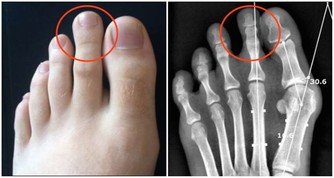

一般來說,額外的一小段臍帶會慢慢脫落、縮回,和腹部融合在一起便形成肚臍眼;「凸肚臍」是因為多出來的表皮組織無法完好地與腹部肌肉融合在一起所形成、或是臍疝氣所造成,但凸肚臍並不會對健康造成影響。

但若是凸肚臍讓你造成不適,或是某些人非常介意美觀,也可以用手術將凸肚臍修整,只要30分鐘的小手術即可完成~!